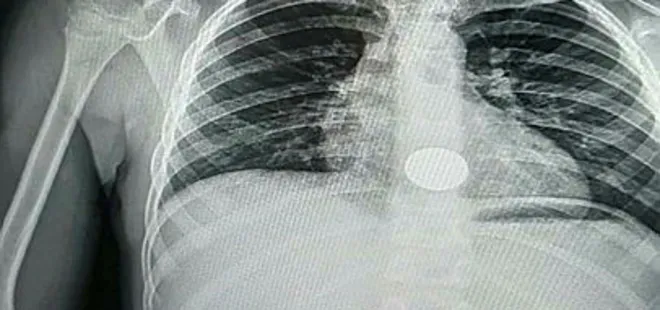

Tire'de oturan Serap ve Hüseyin Kırlı çiftinin oğulları, dün akşam iddiaya göre oyun oynadığı sırada elindeki demir parayı yanlışlıkla yuttu. Durumu fark eden aile, parayı çıkarmaya çalıştı ancak başarılı olamayınca Ali'yi Tire Devlet Hastanesi'ne götürdü. Burada yapılan kontrollerde demir paranın Ali'nin yemek borusunda olduğu tespit edildi. Ege Üniversitesi Tıp Fakültesi Hastanesi'ne sevk edilen Ali Kırlı, ameliyata alındı. Ali'nin yemek borusuna takılan demir para çıkarıldı.

Konuyla ilgili konuşan baba Hüseyin Kırlı, "Oğlum akşam evde oynarken para yuttuğunu söyledi. Hemen hastaneye götürdük. Tire'de ilk müdahale yapıldı, röntgen çekildi fakat operasyon yapılamayacağı söylendi. Ege Üniversitesi Tıp Fakültesi Hastanesi'ne sevk edildik. Orada yapılan operasyonla metal para yemek borusundan çıkarıldı. Şu an eve döndük ve çok şükür sağlık durumu iyi" dedi.